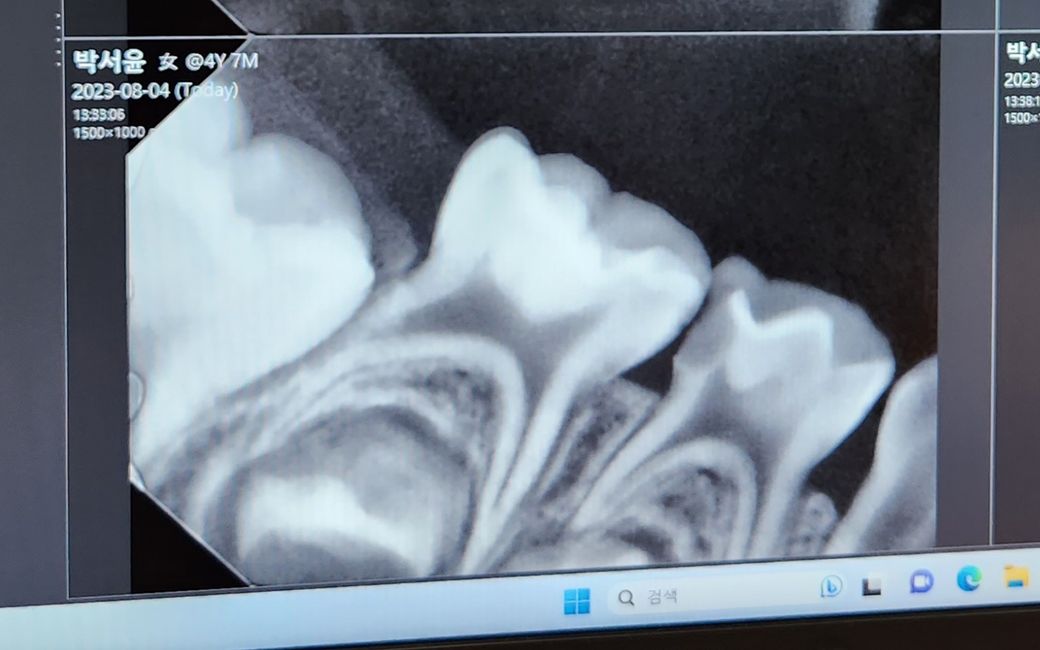

6세아이 어금니 입니다 . 치과에서 신경치료 후 크라운 얘기 듣고 왔습니다

해당사진으로만 봤을 경우에 충치가 이미 신경에영향을 미치는것으로 보입니다.

충치를 제거하게 되면 신경이 노출되기 때문에 신경치료가 필요합니다.

엑스레이 상으로 보면 충치가 굉장히 깊어 보입니다. 충치를 제거하게되면 신경이 노출될가능성이 높고, 신경치료를 하면 은니를 씌우셔야됩니다.

충치를 제거해봐야 정확히 알 수 있겠지만 사진상으로는 신경치료 가능성이 매우 높습니다.